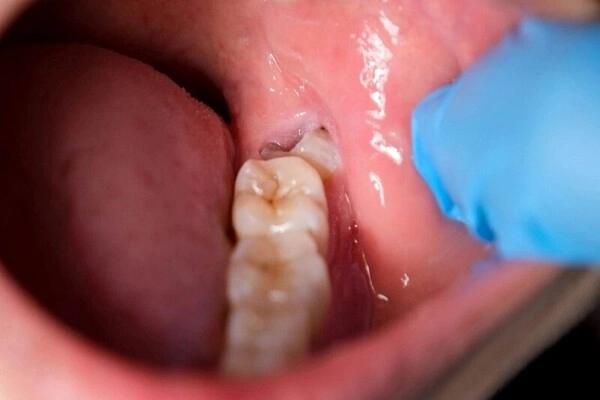

Răng sứ Cercon: Giải pháp phục hình toàn sứ thẩm mỹ caoRăng sứ Cercon là giải pháp phục hình cao cấp giúp tái tạo răng bền đẹp, tự nhiên và an toàn. Cercon có thể duy trì độ bền 15 năm, mang lại nụ cười thẩm mỹ.